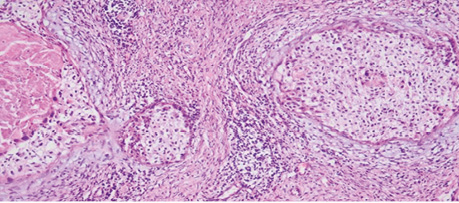

Патогістологічний висновок. З урахуванням морфологічного та попереднього ІГХ-дослідження має місце інвазивна плоскоклітинна HPV-асоційована карцинома шийки матки (low grade) після лікування з явищами вираженого лікувального патоморфозу, пухлина представлена поодинокими дистрофічно-зміненими групами клітин з вираженою лімфоїдноклітинною інфільтрацією, з максимальною глибиною інвазії 2,5 мм (мікроінвазивна карцинома), максимальне горизонтальне поширення — 3 мм, пухлина поширюється цервікальними залозами; лімфоваскулярної, венозної та периневральної інвазії не виявлено. Краї резекції без ознак пухлинного росту. У 10 досліджених тазових регіонарних лімфатичних вузлах справа та зліва метастази пухлини відсутні. Фрагмент тканини шийки матки з вогнищевими розростаннями елементів інвазивної плоскоклітинної HPV-acoційованої карциноми з явищами вираженого лікувального патоморфозу. Компонент інвазивної карциноми представлений окремими поодинокими гніздами пухлинних клітин з вираженими некробіотичними змінами. Реакція на неоад’ювантну терапію відмічається як у клітинах пухлини, так і в навколишній стромі, ядра клітин карциноми звужені, вакуолізовані, визначаються вогнища апоптозу і некрозу, у стромі довкола пухлини відмічаємо виражену хронічну запальну реакцію, виражений фіброз зі склерозом. У нижньому куті праворуч виявлено скупчення збережених ендоцервікальних залоз, деякі кістозно розширені (рис. 5).

Рис. 5. Фрагмент видаленої тканини шийки матки після ПВТ. Збільшення ×40, забарвлення гематоксиліном / еозином

При значному збільшенні у гніздах росту інвазивої карциноми помітні масивні вогнища некрозів у центрі гнізд, збережені клітини пухлини з вираженою вакуолізацією ядер, виражена десмопластична реакція строми довкола зон росту інвазивої карциноми, збережена строма шийки матки з фіброзом та склерозом (рис. 6).

Рис. 6. Фрагмент видаленої тканини шийки матки після ПВТ. Збільшення ×100, забарвлення гематоксиліном / еозином

При такому збільшенні цієї ж ділянки фіксуємо дистрофічні зміни клітин пухлини у гніздах росту інвазивої карциноми, зміни форми та розмірів ядер свідчать про апоптоз, каріолізис та каріорексис, мітотична активність відсутня, значна кількість некротизованих пухлинних клітин. У збереженій стромі шийки матки довкола пухлини ангіоматоз, виражена запальна інфільтрація (рис. 7).

Рис. 7. Фрагмент видаленої тканини шийки матки після ПВТ. Збільшення ×200, забарвлення гематоксиліном / еозином

При значному збільшенні цієї ділянки в центрі наявні збережні елементи інвазивної плоскоклітинної карциноми з вищеописаними некробіотичними та некротичними змінами, добре видно вакуолізацію ядер, запальний перитуморальний інфільтрат представлений лімфоцитами, плазматичними клітинами, з наявністю великої кількості гістіоцитів (рис. 8).

Рис. 8. Фрагмент видаленої тканини шийки матки після ПВТ. Збільшення ×400, забарвлення гематоксиліном / еозином